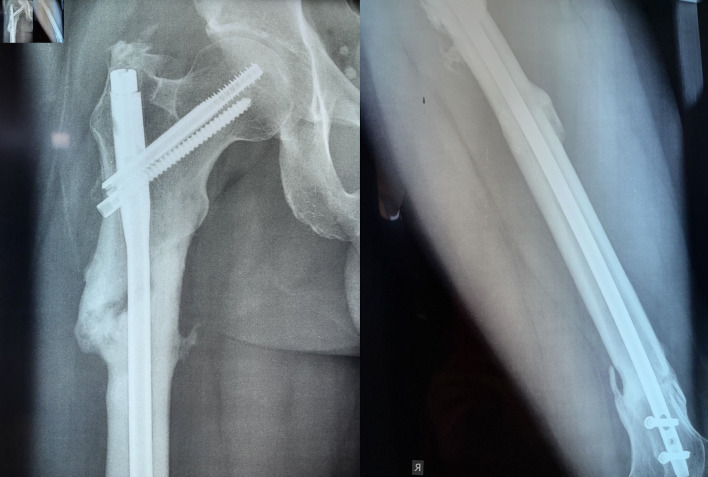

Femoral fractures are indubitably common injuries that can occur either from high-energy trauma in young patients or due to fragility in the geriatric population. Femoral fractures affecting two or more regions of the femur are exceedingly infrequent injuries, ordinarily caused by high-energy trauma and are considered segmental femoral fractures. We present a rare case of a 33-year-old male patient presented to our Emergency Department with multiple femoral fractures at the subtrochanteric, diaphyseal and supracondylar femoral regions, a condition regarded as double segmental femoral fracture. After assiduous consideration of treatment options, intramedullary nailing was employed for osteosynthesis. Fracture reduction was laborious, as an entirely separated femoral fragment was present between the fracture lines. The reaming process required paramount attentiveness as the middle femoral fragment was prone to rotational displacement by the reamer. Finally, the intramedullary nail was successfully placed, and the patient was discharged without complications after 11 days of hospitalization. Currently, the patient is capable of full weight-bearing without crutches. This paper underlines the challenges that double-segmental femoral fractures' treatment can bring on to the orthopedic surgeon.

Abstract Image